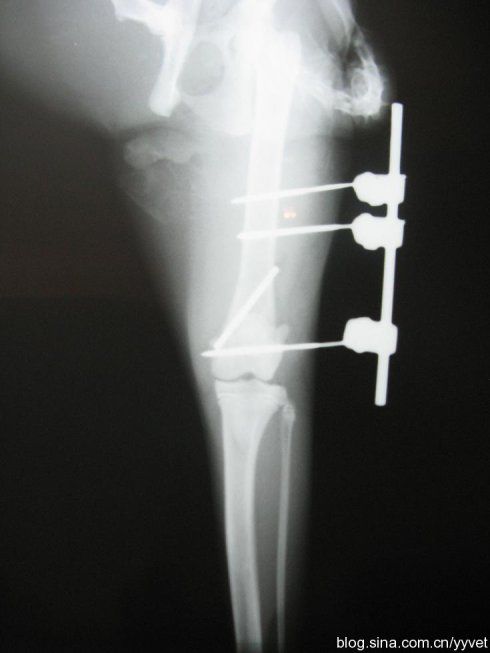

这是一种中和钢板的改版,针对于干部的粉碎骨折,通过透视下监视,使得钢板跨越骨折区域而固定骨折的近端和远端,骨折区域不进行固定。

该类技术主要是强调对位、对线、长度、旋转,中间粉碎可以不用处理,有效保护骨折断端血运,但是需要注意钢板需要有足够的长度,两端固定也需要有足够的螺钉数量。目前容易出现一些骨不连的现象,需要谨慎对待。

应力分散式固定,非应力遮挡式固定,有利于骨痂的塑形。

中心固定在理论上优于皮质外固定,可减小力臂,降低内、外翻成角及内固定失效的发生率。